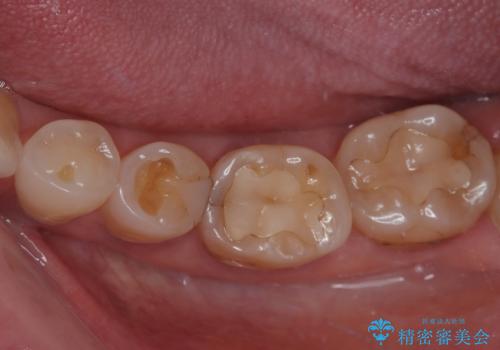

奥歯がたまにしみる フルジルコニアクラウンの補綴治療